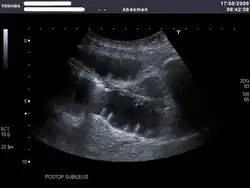

Bild eines postoperativen (Sub-)Ileus im Ultraschall

Bei Ileusverdacht liefert die Sonographie schnelle Hinweise: Man kann bei Vorliegen eines Ileus oft eine typische Pendelperistaltik sehen, d. h., der Darminhalt pendelt hin und her. Auch findet man verbreiterte, übermäßig mit Luft oder Flüssigkeit gefüllte Darmschlingen. Man kann oft den Ort des Verschlusses eingrenzen. Darmabschnitte hinter einem mechanischen Hindernis sind kollabiert (Hungerdarm).[5]